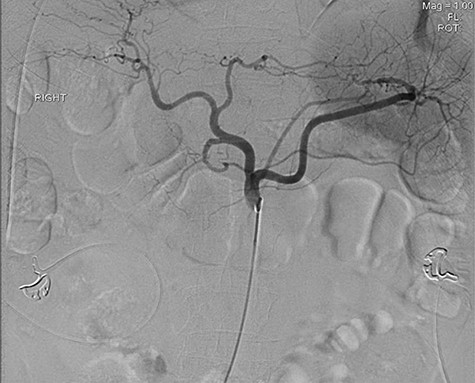

A 56-year-old African American male presented in 2015 with abdominal pain, with associated melena and hematochezia. The patient has a history of chronic back pain for which he takes 600 mg ibuprofen daily, alcohol abuse, tobacco use and a previous GI bleed in 2011, which necessitated 6 units (U) of packed red blood cells (PRBCs) and emergency therapeutic endoscopy. The patient was found to be hypotensive to 76/56 mm Hg, and hemoglobin (Hgb) was found to be 9.4 g/dl, from a previous baseline of 10.6 g/dl. His rectal examination was guaiac positive. A repeat Hgb was found to be 6.5 g/dl. The patient was given 3 U of PRBC and an emergency endoscopy was performed. On endoscopy, the patient was found to have a 6 cm gastric ulcer with an associated vessel underneath of a large clot. Due to the high risk nature of the bleed, it was felt by the gastroenterologist that the patient should undergo an endovascular angioembolization (Fig. 1). The patient was brought to the Interventional Radiology Suite for the procedure. The patient’s right common femoral artery was accessed and the celiac trunk was selected. A subselective common hepatic arteriogram was performed, which demonstrated active extravasation arising from the proximal aspect of the GDA. The GDA was then coil embolized both proximal and distal to the site of bleeding using five microcoils. Repeat arteriogram demonstrated no further opacification of the GDA and no further extravasation (Fig. 2).

Demonstrating coil embolization of the GDA with no opacification